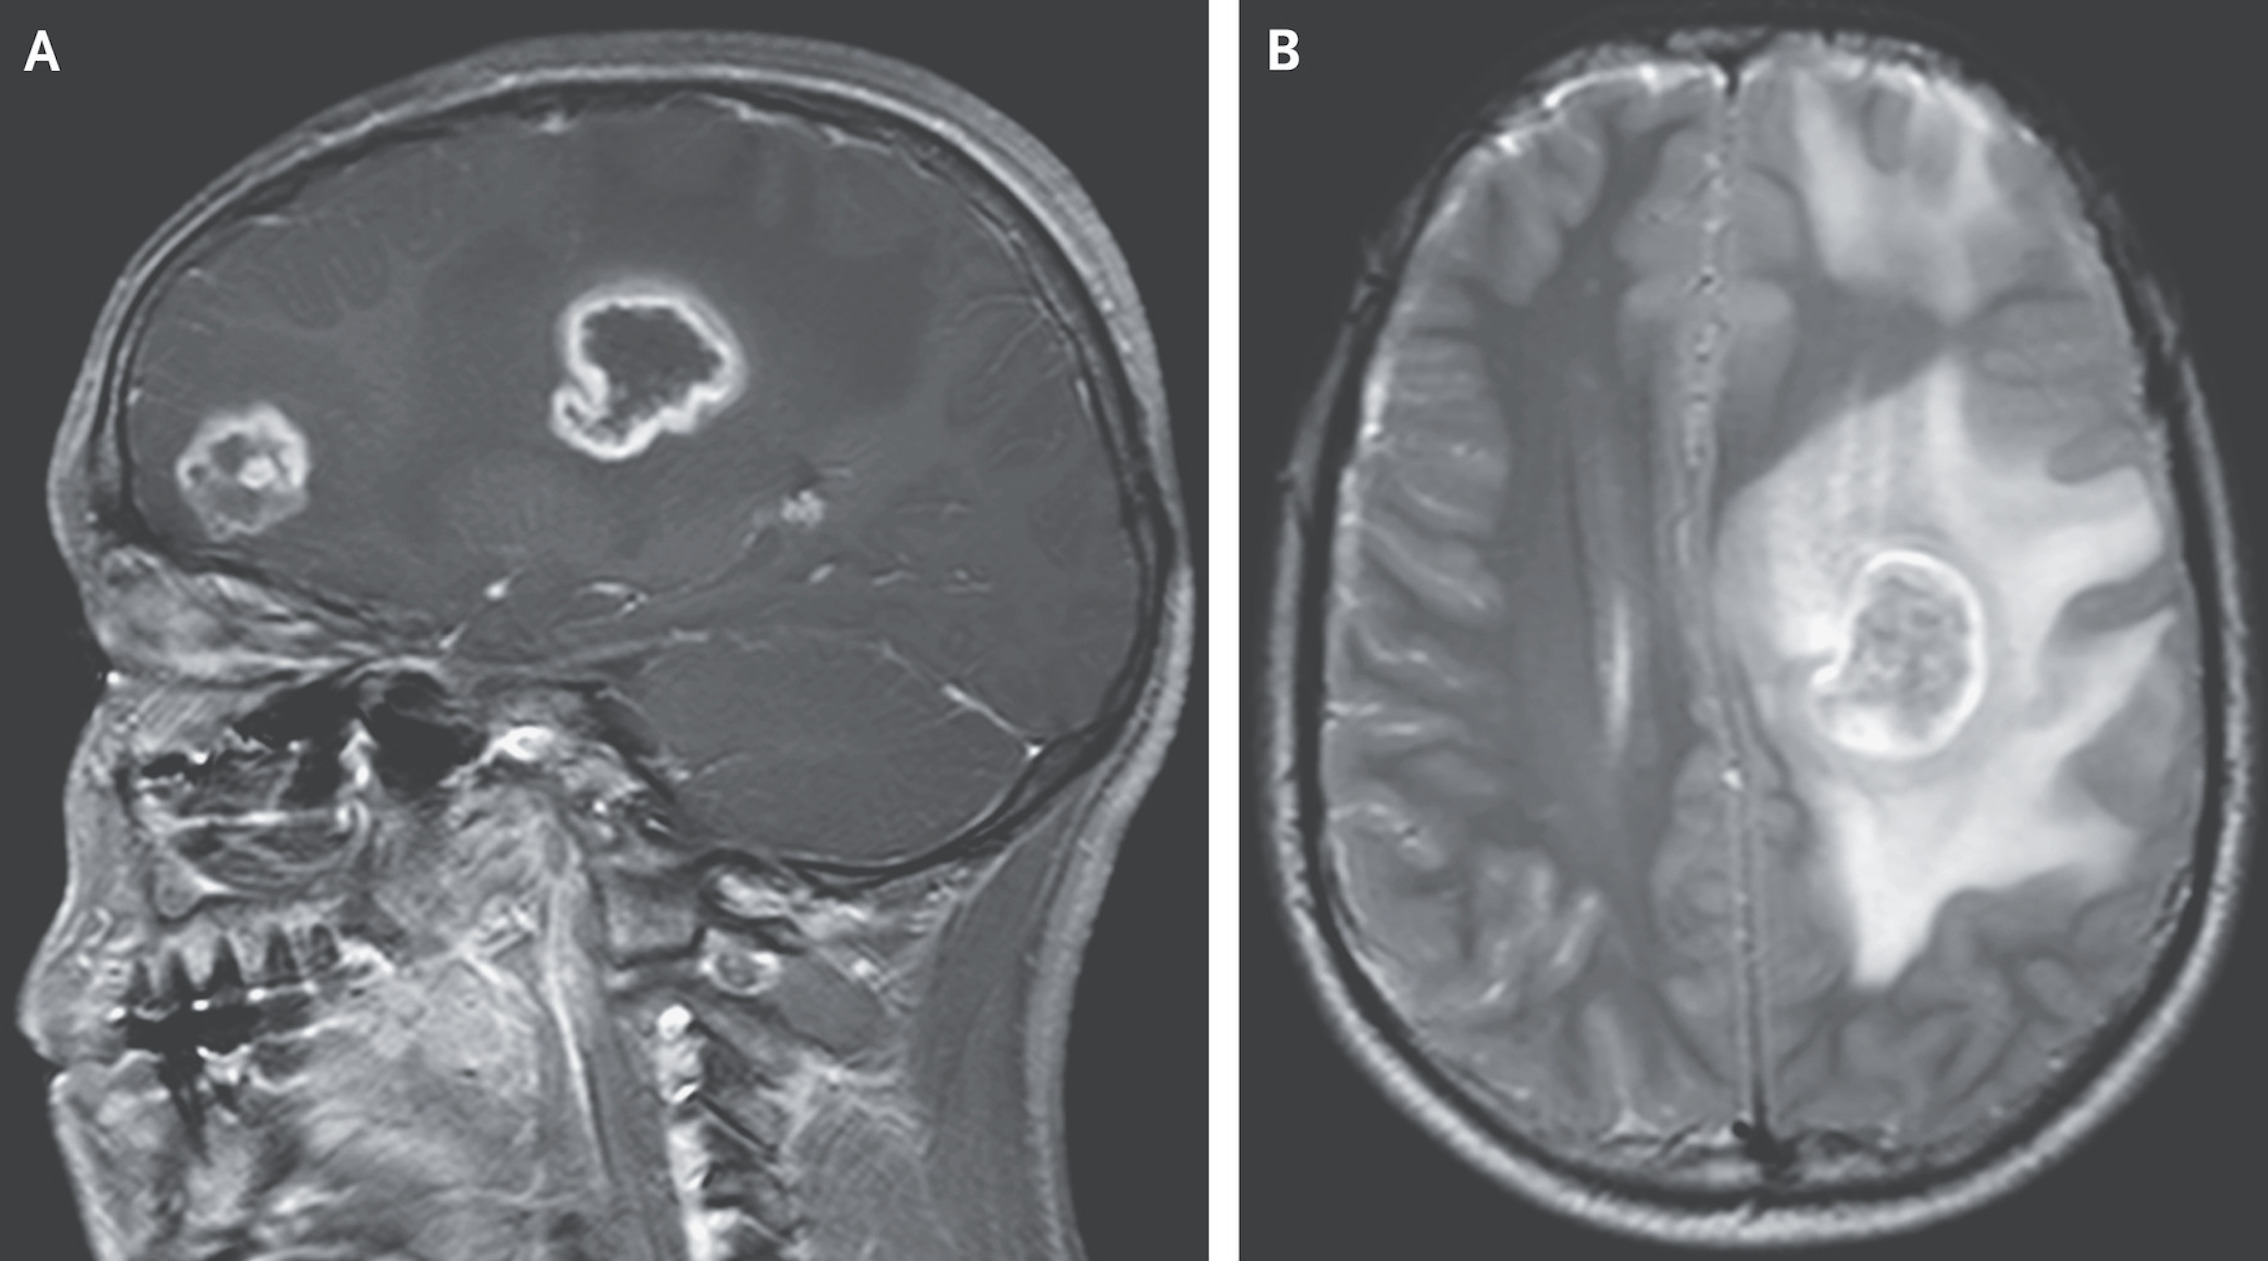

Tumors: Tumors are clumps of cells that grow abnormally from normal tissue. Some tumors in the brain are noncancerous, or benign. Others are cancerous. They may start in the brain, or they may spread from elsewhere in the body (metastatic). They may grow quickly or they may remain stable. Get more information on signs and symptoms of a brain tumor.

In many cases, CT and MRI imaging studies help pinpoint the location, size, and characteristics of the lesions. Blood and other lab tests may also be done to look for signs of infection.

Tumors: Tumors are clumps of cells that grow abnormally from normal tissue.

Some tumors in the brain are noncancerous, or benign. Others are cancerous. They may start in the brain, or they may spread from elsewhere in the body (metastatic). They may grow quickly or they may remain stable. Get more information on signs and symptoms of a brain tumor.

The methods used to find and diagnose brain lesions depend on the symptoms. In many cases, CT and MRI imaging studies help pinpoint the location, size, and characteristics of the lesions. Blood and other lab tests may also be done to look for signs of infection.